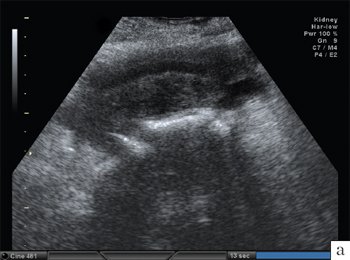

Проведенное УЗИ молочных желез, при котором были осмотрены и мягкие ткани передней грудной стенки и загрудинное пространство, выполнявшееся с использованием линейного мультичастотного (7,5-15 МГц) и конвексного мультичастотного (3,5-5 МГц) датчиков, в режимах серой шкалы, тканевой гармоники, цветового допплеровского картирования (ЦДК, ЭД), установило: в обеих молочных железах отмечается железистый тип строения. Дифференцируется хорошо выраженная протоковая система. Протоки симметричны, расширены более 2 мм в соответствии с нормой для 2-й фазы менструального цикла (рис. 9, 10).

При оценке мягких тканей передней грудной стенки в ретромаммарном пространстве отмечается асимметричность в изображении грудных мышц правой и левой половины. В переднезаднем изображении размеры грудных мышц (малой и большой грудной) в левой половине грудной стенки составляют 10 мм и меньше, справа - 15 мм (рис. 11). Мягкие ткани левой половины грудной стенки сдавлены и оттеснены кпереди структурами новообразования, которое исходит из четвертого межреберного промежутка (рис. 12, 13). Опухоль представляет собой новообразование, напоминающее по форме «песочные часы», и располагается как снаружи, так и внутри грудной полости; основная масса - в загрудинном пространстве. Общий размер опухоли - 7,5х12,6 см (рис. 14-16). Мягкотканный компонент опухоли снаружи от грудной стенки составляет 5,2х7 см.

Рис. 11. Эхограмма мягких тканей симметричных зон здоровой и пораженной сторон грудной стенки.

а) Опухолевые массы (1) сдавливают ткани грудных мышц (2) и молочную железу (3);

б) - Изображение нормального расположения грудных мышц (2) и молочной железы (3).

Рис. 12. Эхограмма фрагмента предгрудинной части опухоли. Прослеживается асимметрия в расположении прилежащих ребер, размеры костного фрагмента одного из ребер уменьшены в горизонтальной и утолщены в переднезадней плоскостях. Датчик 7,5 МГц.

В солидной структуре опухолевых масс определяется жидкостной компонент причудливой трубчатой формы, не сосудистой природы по данным цветокодированной и спектральной допплерографии. При сопоставлении изображения симметричных участков ребер правой и левой половины грудной стенки отмечается асимметричность в их изображении. При УЗИ прилежащих к опухолевым массам костных структур ребер выявлены признаки деструкции. Отмечается нечеткость контуров передней и задней поверхностей прилежащих к опухоли ребер, размеры костного фрагмента одного из ребер уменьшены в горизонтальной и утолщены в переднезадней плоскостях (см. рис. 12-15).

Заключение: основная масса опухоли располагается в грудной полости, распространяясь на костные и мягкотканные структуры грудной стенки. Опухоль оттесняет грудные мышцы и левую молочную железу кпереди. Выявлена деструкция костной части V и VI ребер. Признаков вовлечения в опухолевый процесс левой молочной железы не отмечено.

Компьютерная томография подтвердила данные УЗИ. Биопсия образования позволила установить диагноз мезотелиомы плевры.